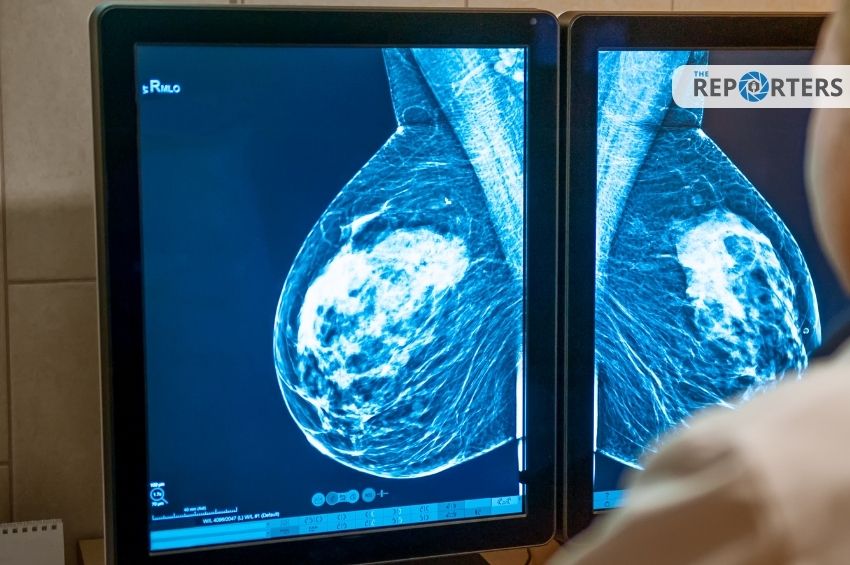

พร้อมกันนี้ นายแพทย์นครินทร์ ยังย้ำว่า มะเร็งเต้านม เป็นมะเร็งที่พบมากในผู้หญิง การตรวจคัดกรองสม่ำเสมอ จึงเป็นสิ่งที่ผู้หญิงทุกคนควรทำ โดยเฉพาะเมื่อมีอายุ 40 ปี ขึ้นไปควรเข้ารับการตรวจคัดกรองด้วยการตรวจแมมโมแกรม และอัลตร้าซาวด์เป็นประจำ หรือหากญาติสายตรงหรือคนในครอบครัวมีประวัติการเป็นมะเร็งเต้านมยิ่งควรต้องเข้ารับการตรวจสม่ำเสมอ และหากพบความผิดปกติ  อาจตรวจเพิ่มเติมหรือบ่อยขึ้น  ขึ้นกับแพทย์วินิจฉัยและเห็นว่าเหมาะสมในแต่ละราย โดยผู้ที่ทำศัลยกรรมหน้าอกสามารถเข้ารับการตรวจแมมโมแกรมได้ตามปกติ และซิลิโคนที่ใช้ก็ไม่เป็นอุปสรรคต่อการตรวจคัดกรองมะเร็งเต้านมแต่อย่างใด ไม่ว่าจะขนาดเท่าใดก็ตาม เพราะขนาดไม่มีผลกับการตรวจ และไม่มีผลกับความเสี่ยงมะเร็งเต้านม